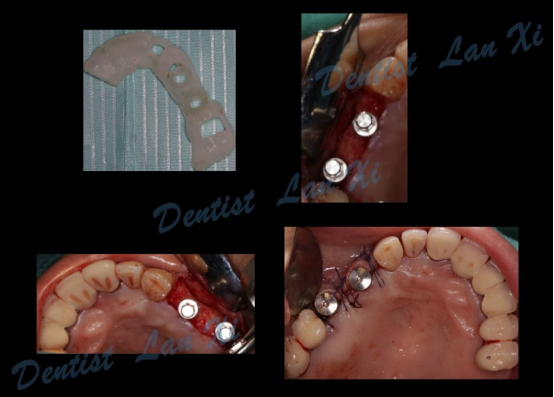

数字化种植导板是通过导板设计软件对CBCT、口扫等一系列数据的系统性分析,辅助口腔种植位点的设计,然后通过3D打印技术等途径进行导板生产,从而实现精准定位的种植手术装置。

简单来讲,数字化种植外科导板(简称导板),是将术前软件设计的种植方案,精确转移至患者口内的个性化手术辅助配件。

第三步:植入及导板设计

第四步:导板制作完成

(目前生成导板的方式主要有3D打印和切削两种方式)

第五步:外科手术

三、过程引导 更微创

数字化种植导板将术前设计方案精准转移,保证了种植体植入位置、方向及角度等的精确性,同时充分利用余留骨量,减少甚至避免了附加手术。